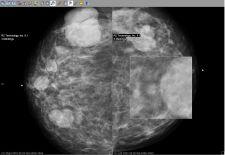

Candelis Inc. will showcase its recently FDA cleared ImageGrid Mammography Web Viewer and ImageGrid Radiology Web Viewer, which are now part of the ImageGrid RIS/PACS Appliance technology suite, at SIIM 2008.

The ImageGrid Mammography Web Viewer and Radiology Web Viewer are diagnostic tools aiming for timely access to medical imaging studies from anywhere and at any time to improve patient care. Both viewing applications are highly scalable and designed to

accommodate multiple concurrent users without the need to invest in additional servers, said the company. As a multi-modality visualization solution, the viewers allow radiologists to view all relevant prior studies from one workstation.